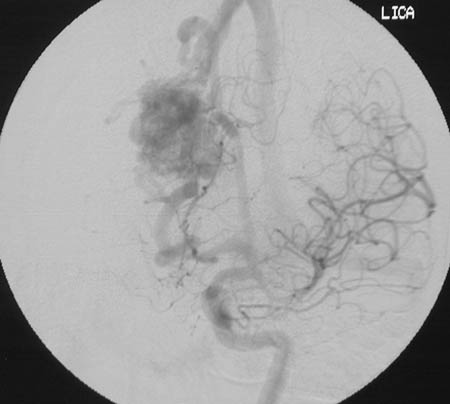

| In the angiogram above there is a vascular malformation in the right medial frontal lobe. There is contrast in the arterial branches of the left internal carotid, while there is continued venous drainage from the vascular malformation on the right. This vascular malformation was supplied by a pericallosal branch of the anterior cerebral artery. This patient had a history of severe headaches for years. Some patients may have seizures. In the axial MRA image below, the vascular malformation can be seen to drain into the superior sagittal sinus. |